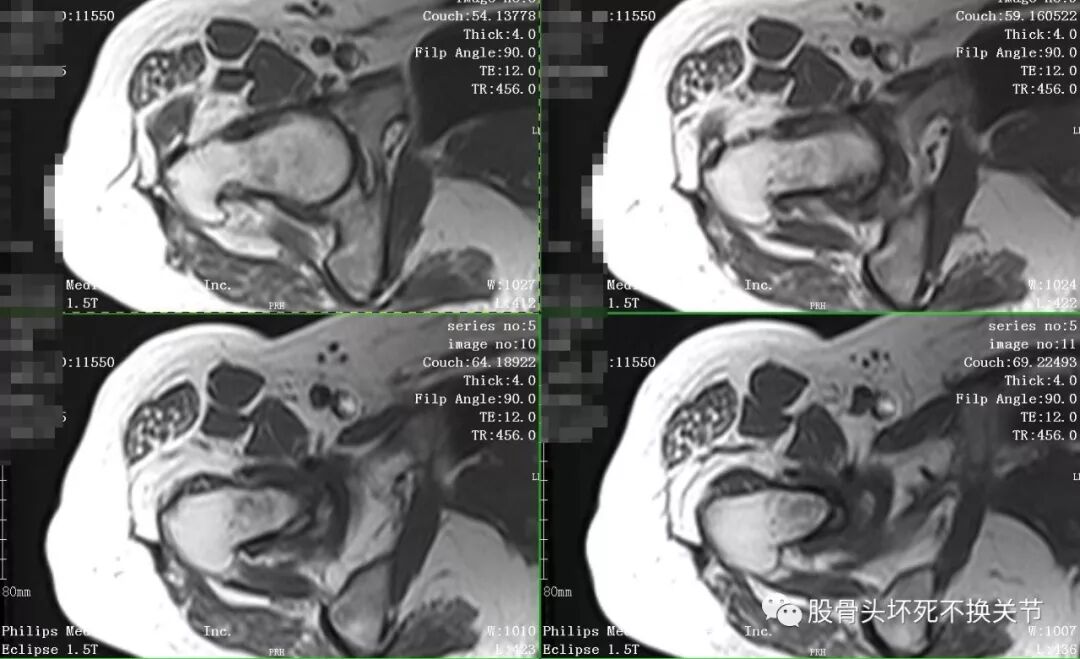

又过了半年,再次复查X线片:

股骨头除了骨密度更低之外,看不出来有特殊变化